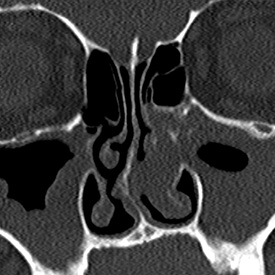

정밀 내시경

첨단 3D-CT와 내시경 촬영을 통해 코 내부의 상태와

축농증 정도 등을 확인합니다.